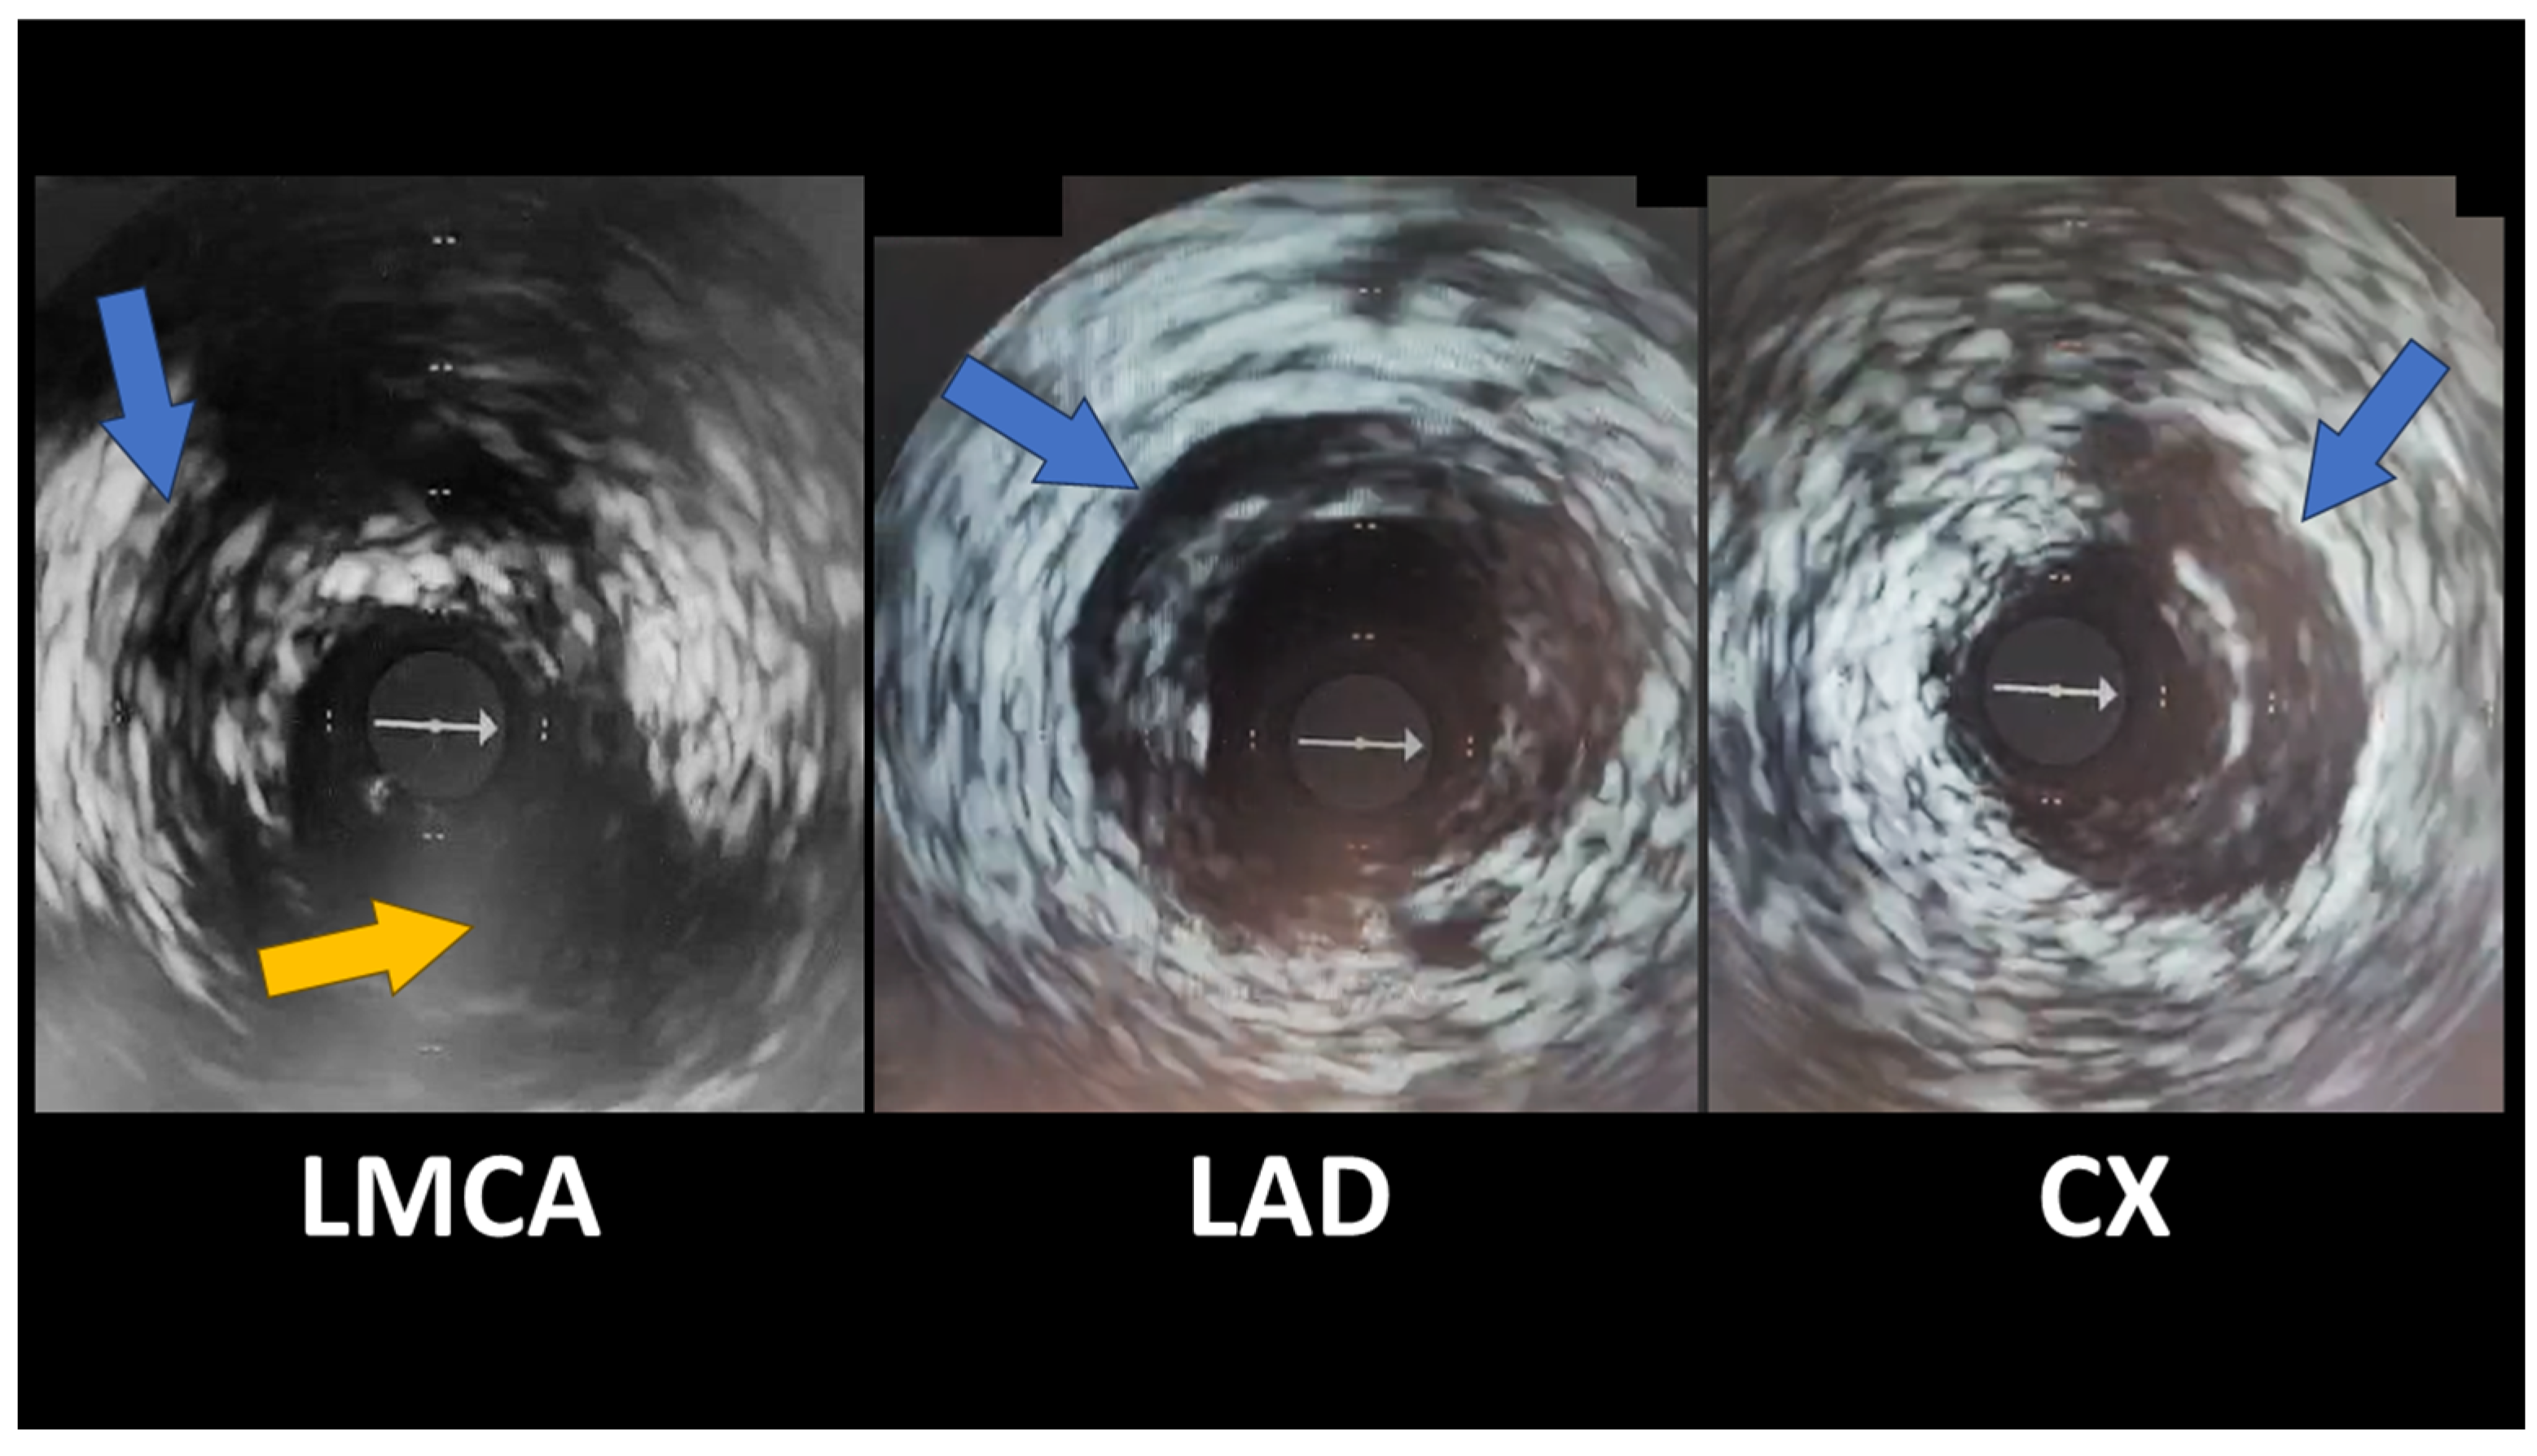

Spontaneous Coronary Artery Dissection Involving the Left Main with Extension to Left Anterior Descending Artery and Left Circumflex Artery: Diagnostic and Management Challenges

Rusali, C.A.; Cojocaru, L.; Lupu, I.C.; Uzea, C.-D.; Rusali, M.L. Spontaneous Coronary Artery Dissection Involving the Left Main with Extension to Left Anterior Descending Artery and Left Circumflex Artery: Diagnostic and Management Challenges. Diagnostics 2025, 15, 61. https://doi.org/10.3390/diagnostics15010061